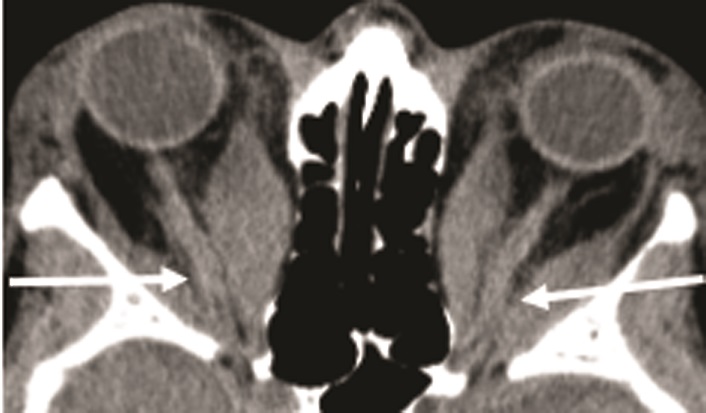

10. Fig. 6. Clinical manifestations of EOP with involvement of EOM and RBC. b - MSCT, axial projection: compression of the optic nerve (white arrows) in a patient with a severe form of image intensifier, complicated by optical neuropathy. | |

| Subject | ||

| Type | Other | |

View

(601KB)

|

Indexing metadata ▾ | |